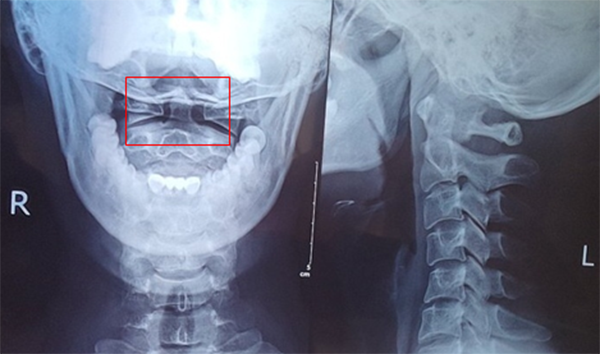

一張頸椎X線正側(cè)位片求得真因

(請(qǐng)注意是張口位,否則查不到病灶)

頸椎X線檢查結(jié)果:頸椎生理曲線變直、寰枕間隙略窄,鉤椎關(guān)節(jié)增生,右側(cè)寰齒間距窄,兩側(cè)寰齒間距差值大于2mm,左側(cè)寰椎側(cè)塊較右側(cè)略寬(見(jiàn)圖紅框中)。

X片結(jié)果,肯定了醫(yī)療團(tuán)隊(duì)的分析思路,明確了臨床診斷:頸椎病,寰樞關(guān)節(jié)脫位。